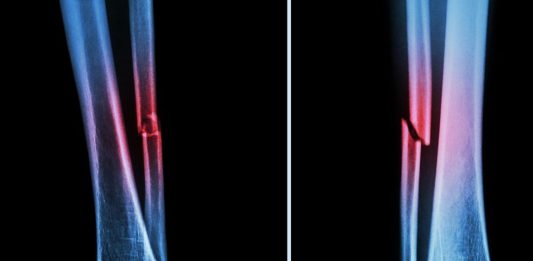

Tibia ve fibula Şaft Kırığıkları, en yaygın uzun kemik kırıkları arasında yer alsa da, izole fibula kırıkları nadir görünmektedir ve izole şaft kırıklarının insidansı üzerine çok az literatür bulunmaktadır. Bunun bir nedeni ise izole fibula şaft kırıklarının büyük çoğunluğunun non-operatif olarak tedavi edilmesidir. Bu yazıda şaft kıkları anlatılmıştır. Fibulanın diğer kırıklarına aşağıdaki linklerden ulaşabilirsiniz. Fibula … Fibula Kırığı okumayı sürdür